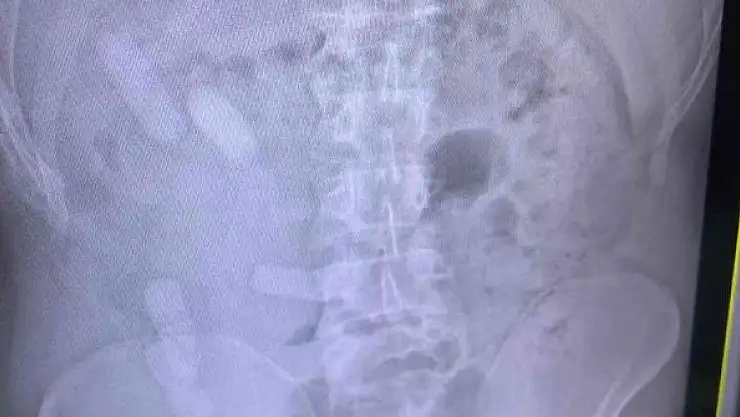

Edinilen bilgiye göre Sivas İl Jandarma Komutanlığı ekipleri, D-100 karayolu Yıldızeli ilçesi geçişinde Lasy isimli narkotik köpeği ile yol denetimi gerçekleştirdi. İranlı yolcuları taşıyan 84 AA 845 plakalı otobüste yapılan aramada A.E. (34) isimli şahsın üzerinde, içerisinde reçine esrar bulunan 140 kapsül ele geçirildi. Şüphe üzerine A.E. isimli İranlı şahsa çekilen röntgen filminde midesinde de 15 kapsül olduğu anlaşıldı. Kapsüller doğal yollarda çıkartıldı. A.E. jandarma ifadesinin ardından çıkartıldığı adli makamlarca tutuklanarak cezaevine konuldu.